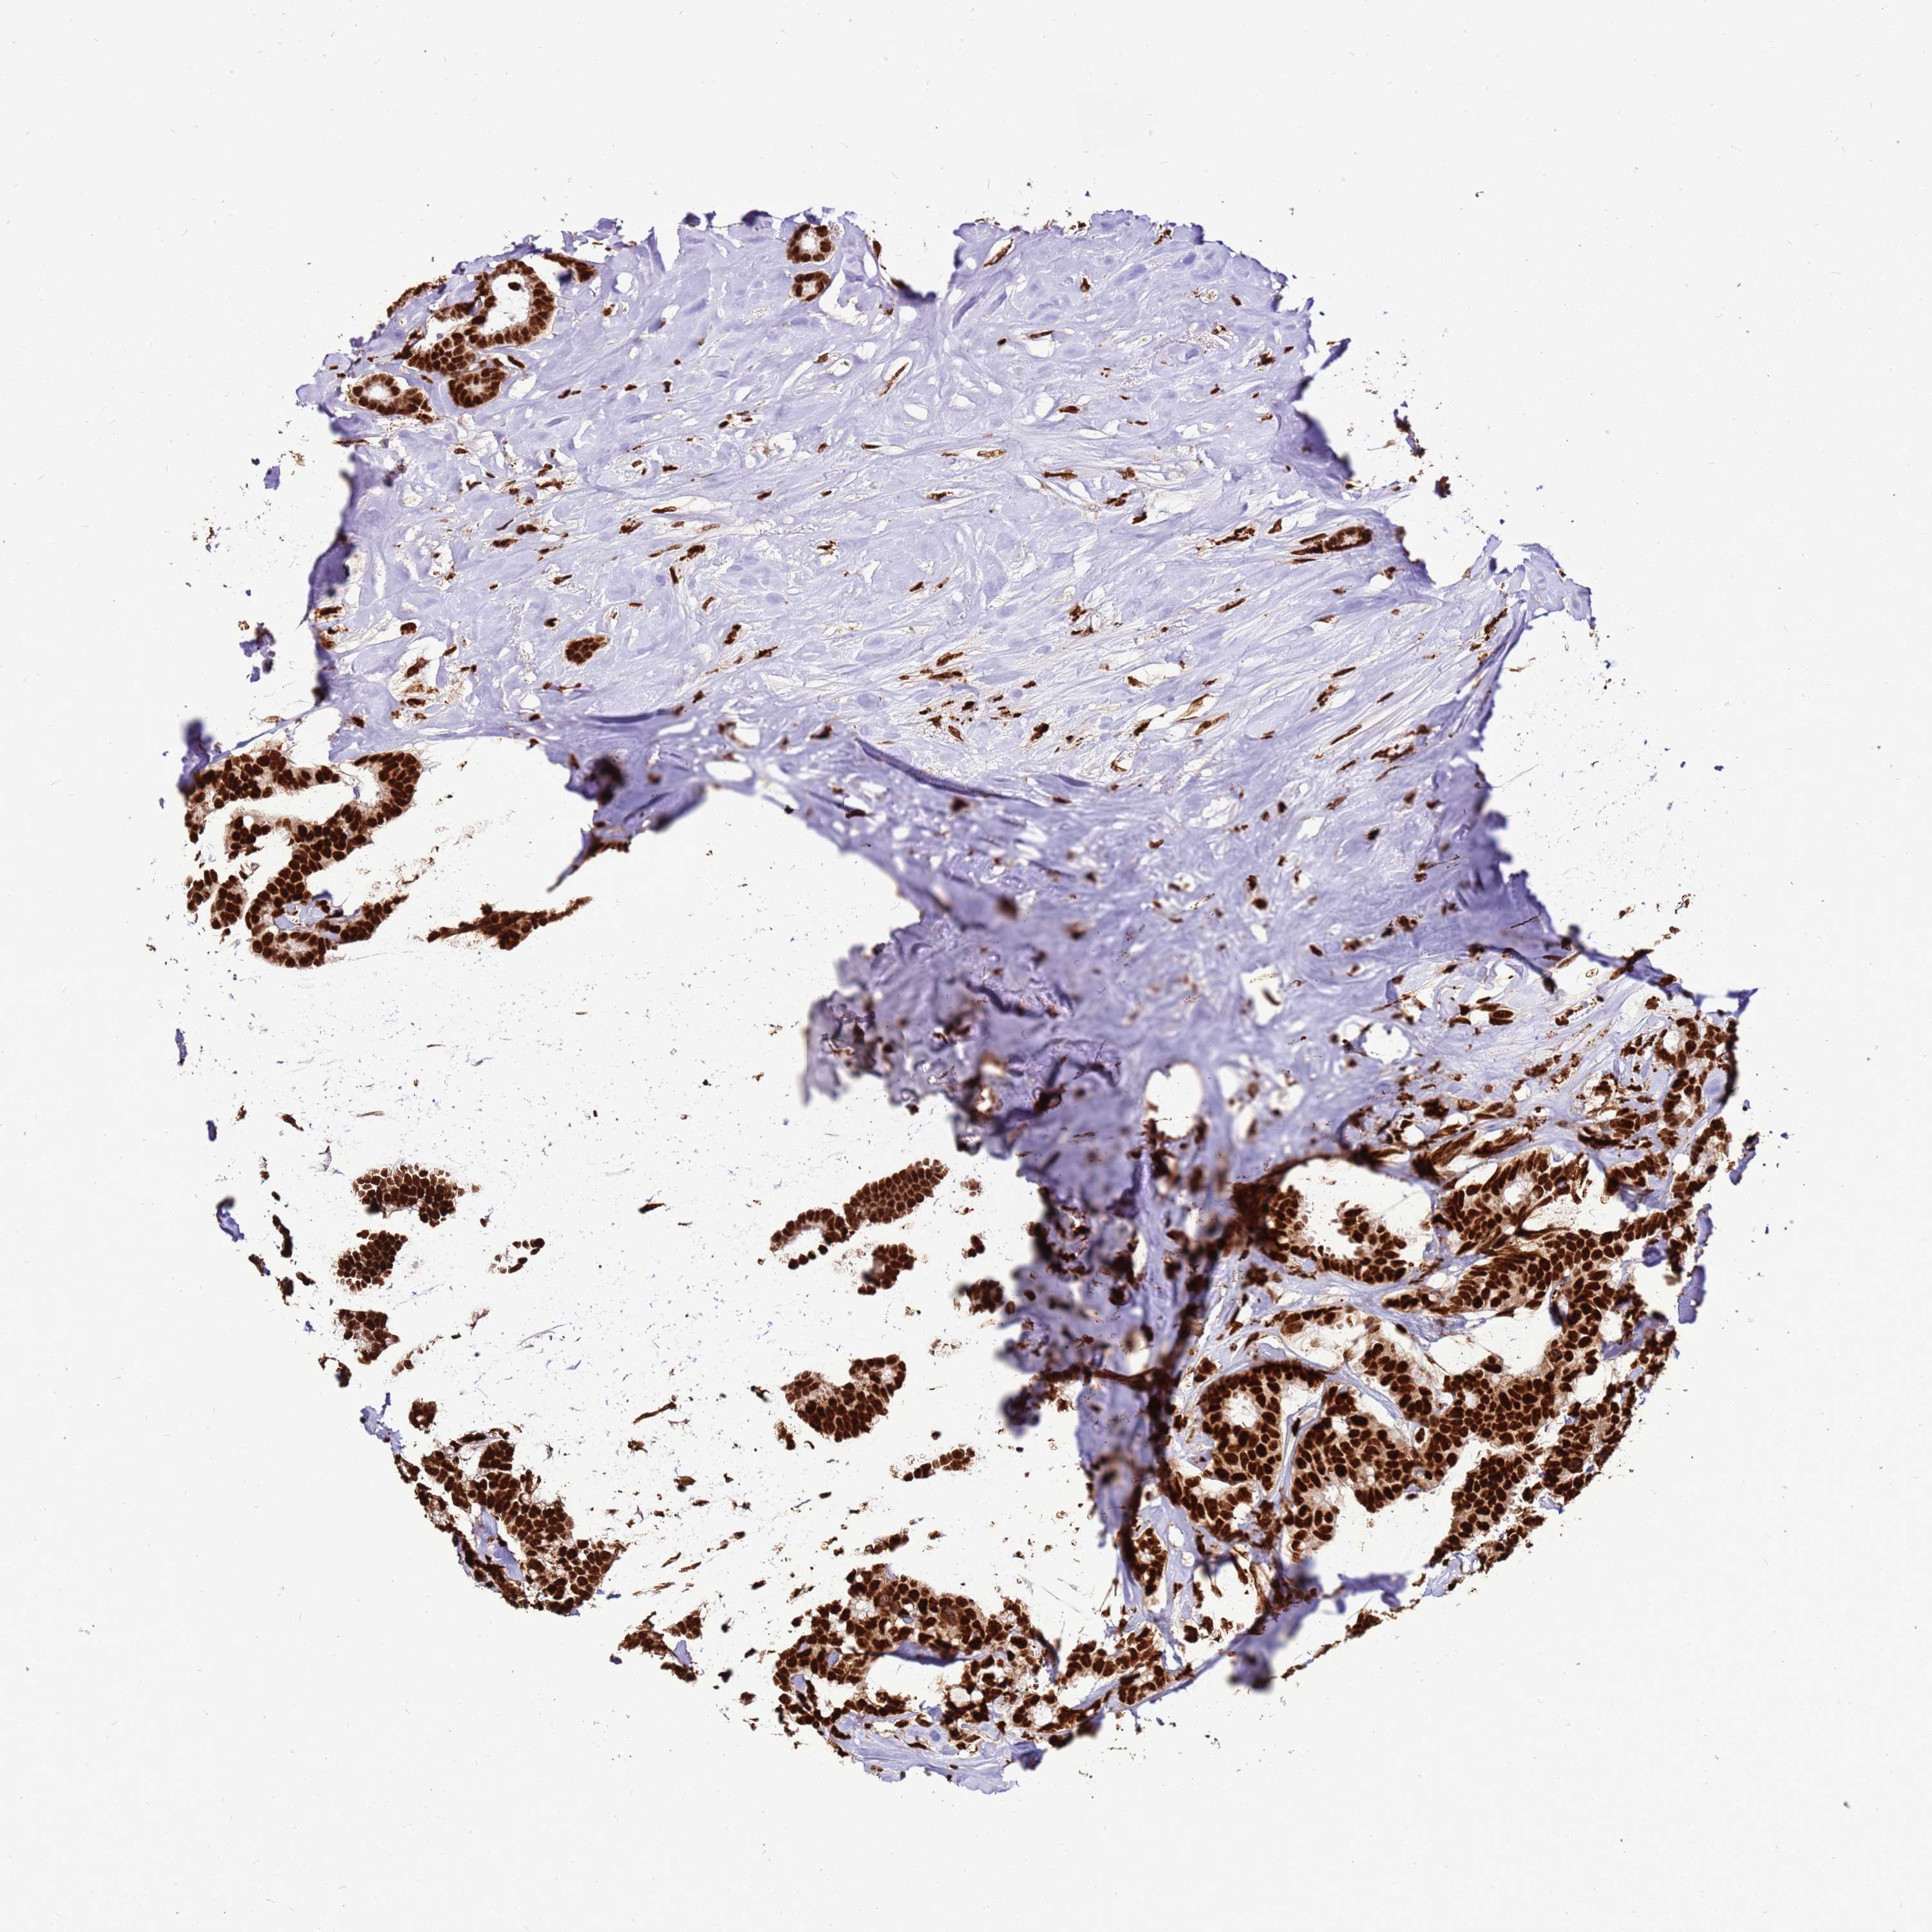

CANCER BREAST CANCER Show tissue menu

BRCA TCGA BRCA VALIDATION PROTEIN EXPRESSION

Breast cancer

Human cancer

Breast invasive carcinoma